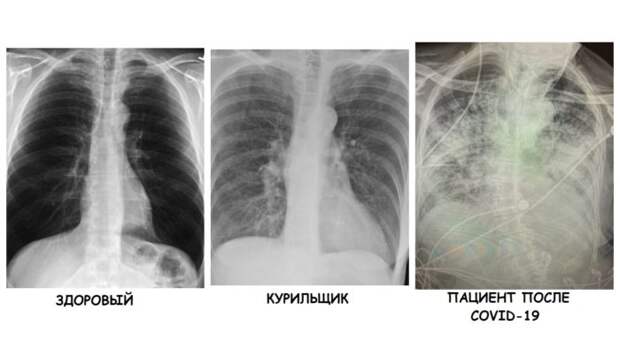

Нормальная рентгенограмма легких: что нужно знать

Раздел: Мудрость в объективе